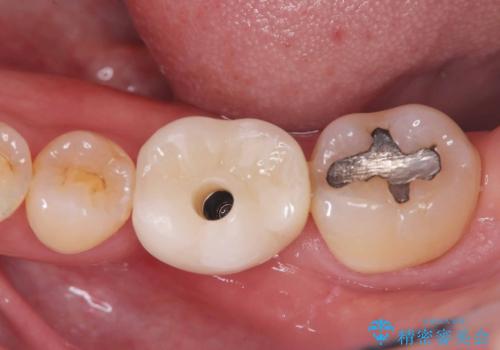

インプラント治療は手術が一度で完了し、術後の痛みもほとんどありませんでした。

機能面・審美面ともに大きく改善され、患者様にも大変ご満足いただけました。